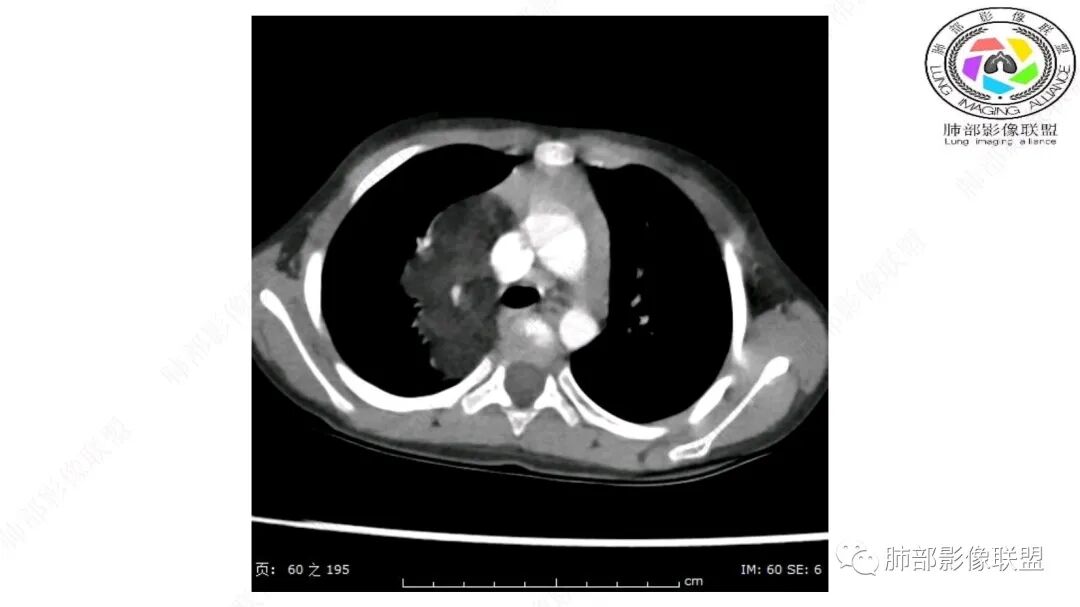

右上纵隔混杂密度肿块,边缘光整,与纵隔分界清,其内多发脂肪密度,增强无明显强化,其内血管穿行,考虑纵隔脂肪母细胞瘤,鉴别畸胎瘤,脂肪肉瘤。

三岁小儿,右侧纵隔巨大脂肪密度肿块,肺动脉穿行其中,密度欠均匀,未见明确实性成分,纵隔脂肪母细胞瘤,冬眠瘤鉴别纵隔脂肪增多症(多弥漫对称)。

患儿3岁 咳嗽检查发现纵隔占位。右肺上叶受压表现,占位以脂肪组织密度为主,似见分隔,首先考虑为脂肪母细胞瘤,鉴别脂肪瘤,畸胎瘤。

幼儿,右上纵膈团块,脂肪密度,内见分隔,增强病灶内见血管穿行,结合患者年龄,考虑脂肪母细胞瘤,鉴别脂肪瘤。

右肺门上方,位于纵隔胸膜旁见巨大肿块,脂肪为主混合密度,内见细小血管影,肿块最大长径与纵隔胸膜平行,包绕右肺上叶肺动脉,右肺上叶及纵隔结构推压,无侵蚀破坏,良性肿瘤,起源纵隔胸膜血管平滑脂脂肪瘤。

跨肺门,包绕肺血管分支,邻近肺组织受压肺不张。

可以看到造影剂进入的丛状结构

密度不均,非纯脂肪成分。斑片状密度略高区域有轻度填充式强化。

婴幼儿,病变较大,跨肺门,分叶,富含纤维或黏液、含成熟脂肪,破坏力弱或无,浸润性生长模式不明显,未见远处转移。

病灶属于交界区,主体位于肺内,占位效应明显,前方突入胸壁,胸腺受压变形,胸膜显示欠清楚;病灶包绕上叶肺动脉;似乎有体动脉供血。符合肺内的点:包绕上叶肺动脉分支;符合纵隔的点:前方似乎突入胸壁,与胸腺关系比较密切,但是与上腔静脉的关系提示病灶不支持纵隔来源,前纵隔的常规会将上腔静脉受压后移、外移,这是不符合的。

手术记录:见右肺上叶肿物,肿物与右肺上叶关系密切。与纵隔无粘连,逐步分离肿物,见肿物大小约6cm*5cm,边界清楚,于右肺上叶粘连,边界清楚,肿物包绕右肺上叶血管及支气管。超声刀逐步游离肿物,完整切除肿物,右肺上叶肺组织无破溃,表面无出血。